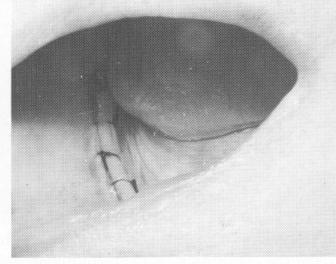

Before the impression is taken, the lingual grooves are made. The length of these grooves is determined by the contour of the bone's lingual surface. If there is a severe undercut from the crest of the ridge ex-tending downward to the lingual surface, the grooves must start near the crest of the ridge and proceed downward to the point where the ridge turns sharply inward. Usually when these severe undercuts exist, the lingual grooves are much shorter. The grooves are made with a narrow tapering diamond point bur and are usually   to 1 mm. deep and

1 mm. wide   the depth and width of the implant

fingers. The grooves should have no sharp line angles (Fig. 12-50) .

Fig. 12-50. The lingual notches are usually 1/2 to 1 mm. deep and 1 1/2 mm. wide, and all line angles are rounded out.

1 Lingual notches in jaw are half to one mm deep, & one & half mm wide